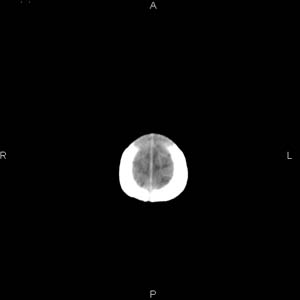

患者男,27天,出生后正常,今天中午在母亲怀里抱着吃奶在放下睡觉时发现后枕部慢慢出现一包块,来查头颅ct。无外伤史。包块内ct值47-51hu。请大家讨论。

支持脑膜脑膨出,双侧侧脑室三角区周围脑白质对称性低密度影,考虑缺血缺氧性脑病或肾上腺性脑白质营养不良。

\"中午在母亲怀里抱着吃奶在放下睡觉时发现后枕部慢慢出现一包块,包块内ct值47-51hu。

颅骨无缺损,骨缝无增宽.支持头皮血肿(血管破裂)